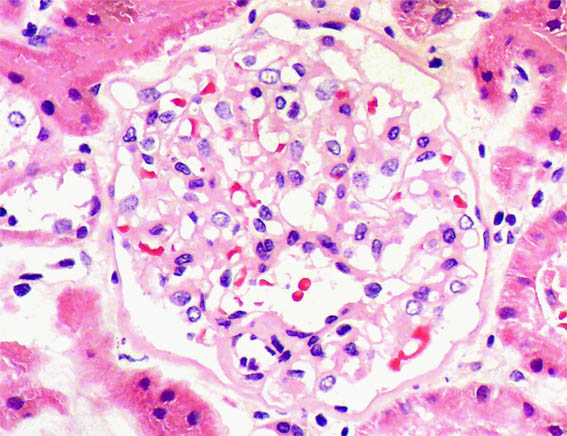

Figure 2. H&E, X400.